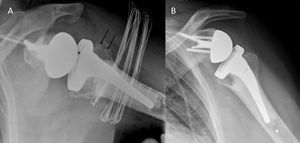

Reverse shoulder arthroplasty for malunion of proximal humeral fracture. A) Anteroposterior radiograph of a malunited proximal humerus fracture; B) post-operative radiograph of the fracture sequelae treated with reverse shoulder arthroplasty.

A) Anteroposterior radiograph of a failed anatomic total shoulder arthroplasty; B) Anteroposterior post-operative radiograph after reverse shoulder arthroplasty.